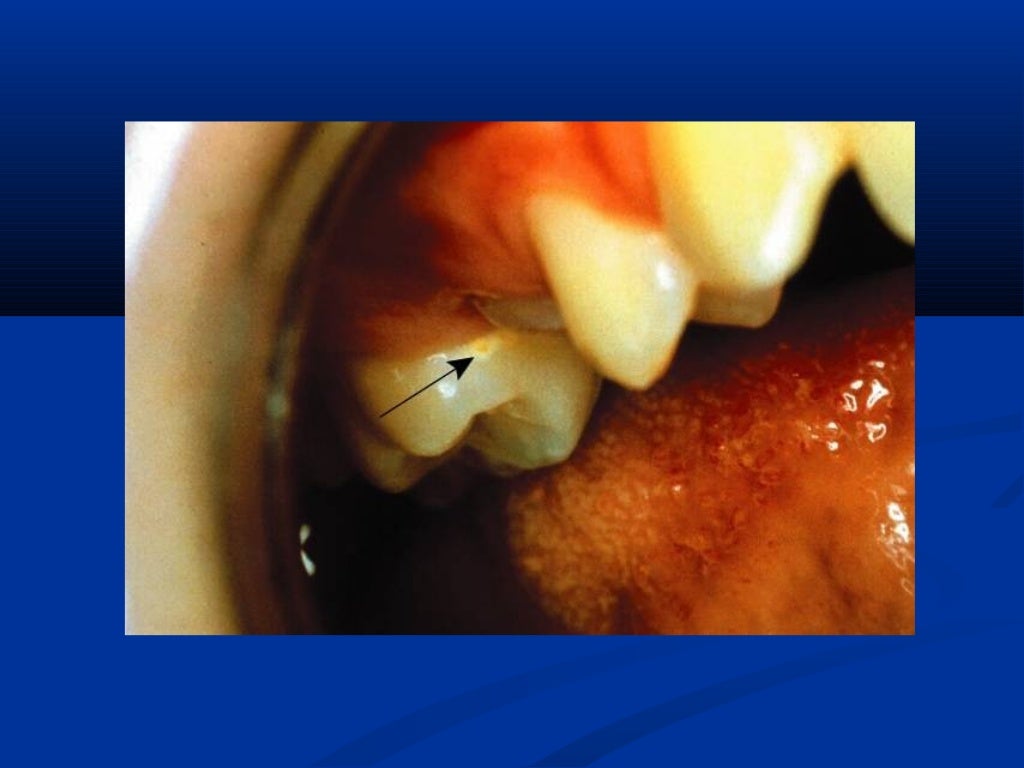

Caries prevention

caries prevention i